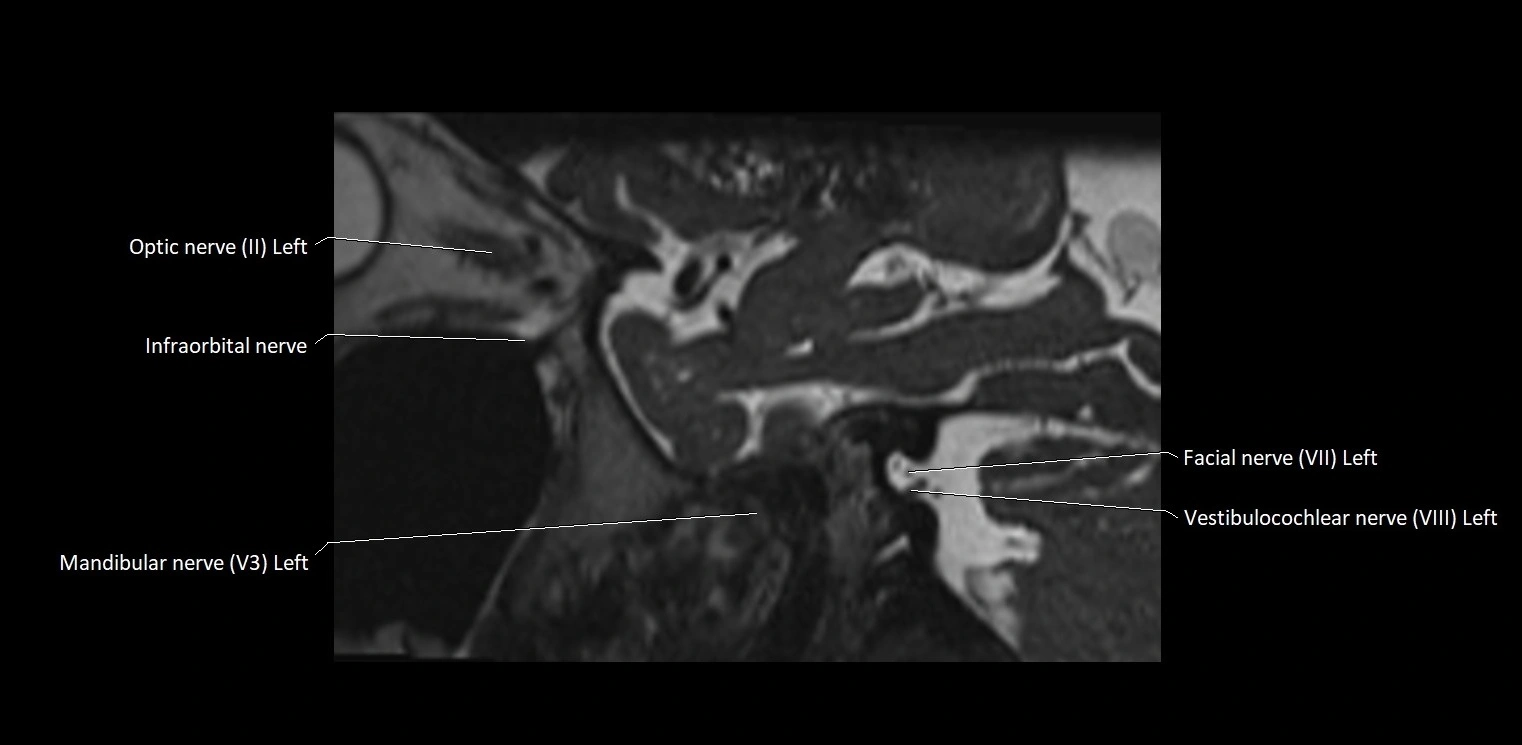

• The abducens nerve is a small, thin, linear structure

• Best visualized on high-resolution T2-weighted 3D MRI sequences (e.g., FIESTA or CISS)

• Seen as a hypointense (dark) line running from the brainstem at the pontomedullary junction, traversing the prepontine cistern, and entering Dorello’s canal under the petrosphenoidal ligament, then into the cavernous sinus, and finally the orbit

• May be challenging to visualize in standard MRI due to its small size

• Pathology may be inferred by absence, displacement, or enhancement of the nerve